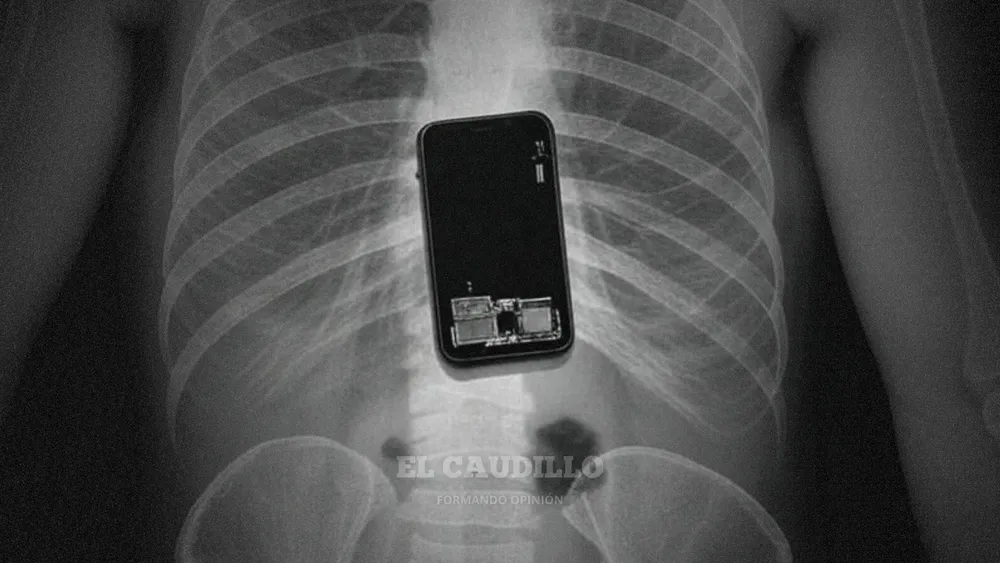

Los hechos se desarrollaron en una celda de la Brigada de Investigaciones 2 de Orán. En la mañana de ese día, un detenido solicitó ser trasladado urgentemente al hospital a causa de un intenso dolor abdominal. Durante su atención médica, confesó que un compañero le había introducido un teléfono celular por vía anal la noche anterior.

Tras la realización de una radiografía, los médicos confirmaron la presencia del celular en su estómago, lo que resultó en una cirugía urgente para extraer el dispositivo. Con la condena firme, el juez también ordenó la extracción de ADN del acusado para su inscripción en los Bancos de Datos Genéticos.